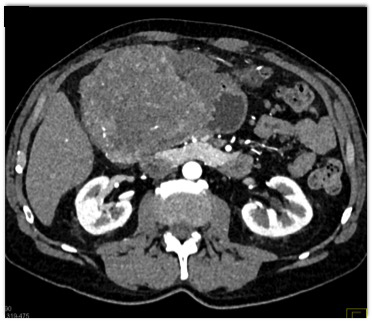

The best diagnosis in this patient with right upper quadrant pain is?

Gastric adenocarcinoma

GIST tumor of the stomach

Hepatoma

Cholangiocarcinoma